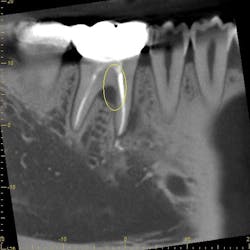

Periodontal ligament stem cells (PDLSC), located within the periodontal ligament, are of particular interest as these progenitor cells are involved in the processes of repairing alveolar bone and periodontal tissues that surround teeth. Specifically, exosomes derived from these cells (periosomes) may be the promising exosome of choice for treating gum disease. Exosomes for periodontitis (termed periosomes) have already been utilized in humans, and the results have been promising. The authors of this article have been among the first groups to investigate periosomes for bone regeneration in patients (figure 1). Periosomes exhibit essential roles in biological mechanisms, including the stimulation of cellular proliferation, angiogenesis promotion, and the enhancement of tissue repair capabilities.2

The case in Figure 1 presents a patient who was losing significant bone around a back molar. The after photo represents a new radiograph taken six months later, displaying new bone regeneration using periosomes.